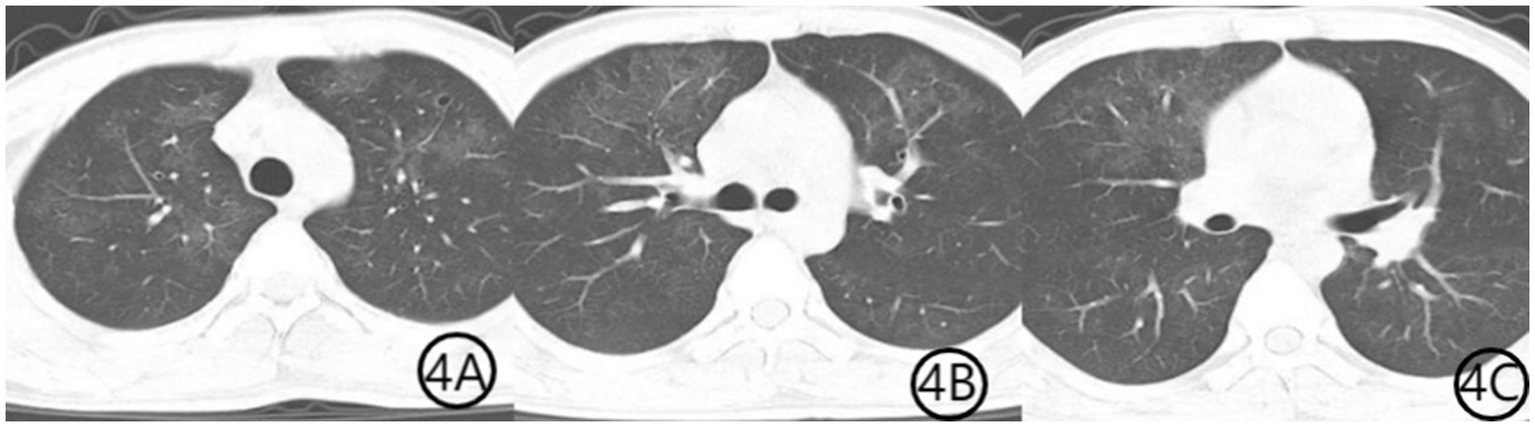

Figure 4

(A–C) Chest CT scan 1 month after initiation of treatment. Axial CT images show further resolution of bilateral diffuse ground-glass opacities, indicating continued radiological improvement and near-complete recovery from pulmonary infection.